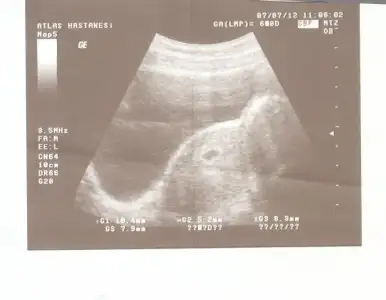

canim ya masallah, gerci pek cozemedim, neresi neresi, su ortadaki nokta kalbi galiba:))) saglikla buyusun insallah, darisi basimiza:)))

canim ya masallah, gerci pek cozemedim, neresi neresi, su ortadaki nokta kalbi galiba:))) saglikla buyusun insallah, darisi basimiza:)))